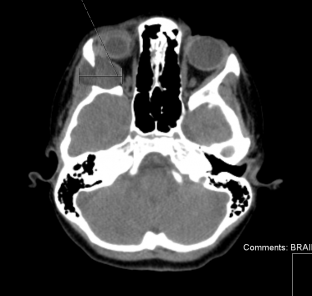

If a deeper cyst is suspected, a computed tomography (CT) or magnetic resonance imaging (MRI) is indicated. It is described as a well-circumscribed lesion with a hyperdense wall and hypodense contents. Bony remodeling is present in 85% of cases.[2] Computed tomography can also rule out a dumbbell configuration, with part of the lesion in the orbit and part in the temporal fossa, connected through a bony defect at the suture line.[3][4]